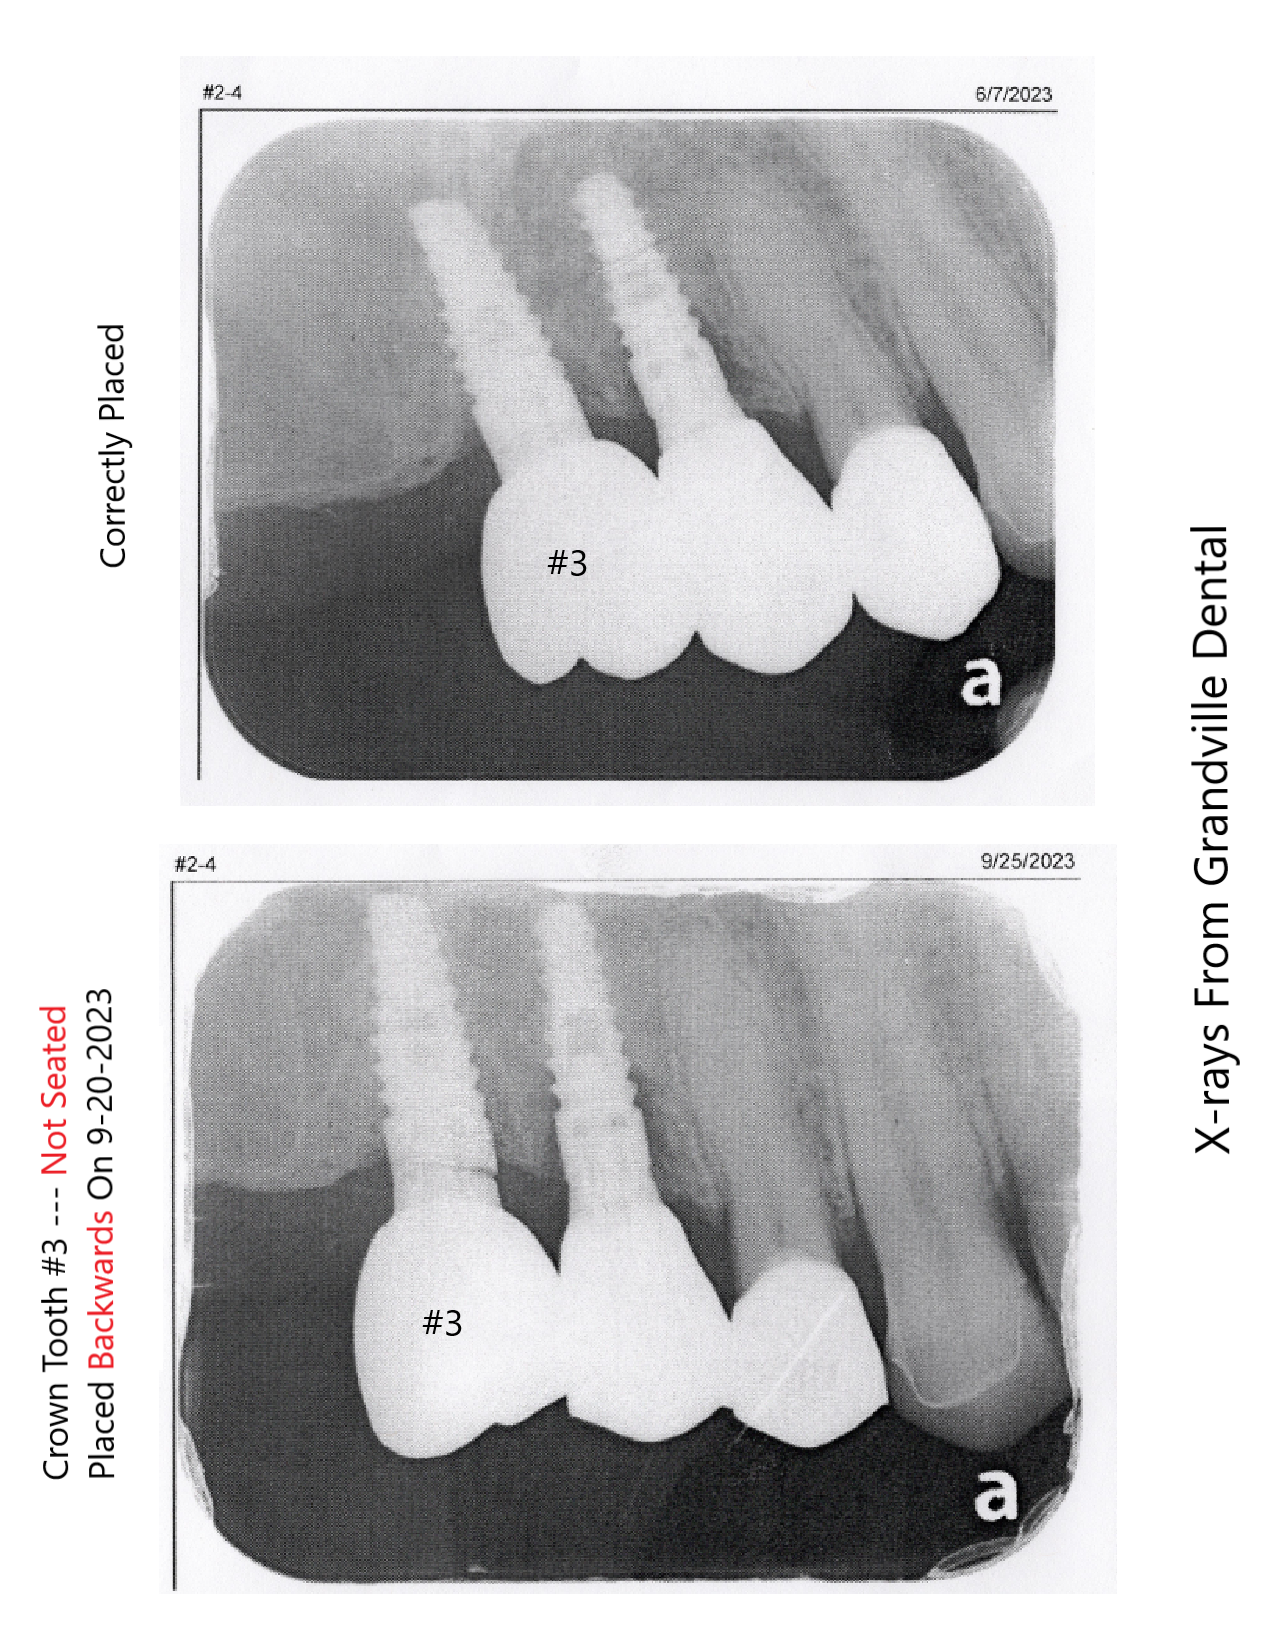

Fraudulent Doctors Doctor doesn't know how to properly do a clinical exam and instead has helped there colleague scam a patient. I am unable to get my teeth fixed because of Dr. Palmer through a biased clinical exam through the Michigan Dental Association with Dr. Palmer where the doctor from Grandville Dental Health Center that did the work was present. Dr. Palmer was bribing me with a check to sign a release form to say the doctor did nothing wrong. Who offers a check to someone before the clinical exam even took place. ...Ā read more